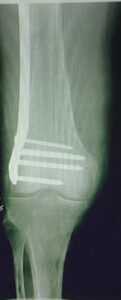

- Πολύ περιφερικό κάταγμα στο γόνατο με δύσκολη αντιμετώπιση.

- Διόρθωση του άξονα και της στροφής του οστού με πλάκα Liss μηριαίου και διαδερμική τεχνική (MIS).